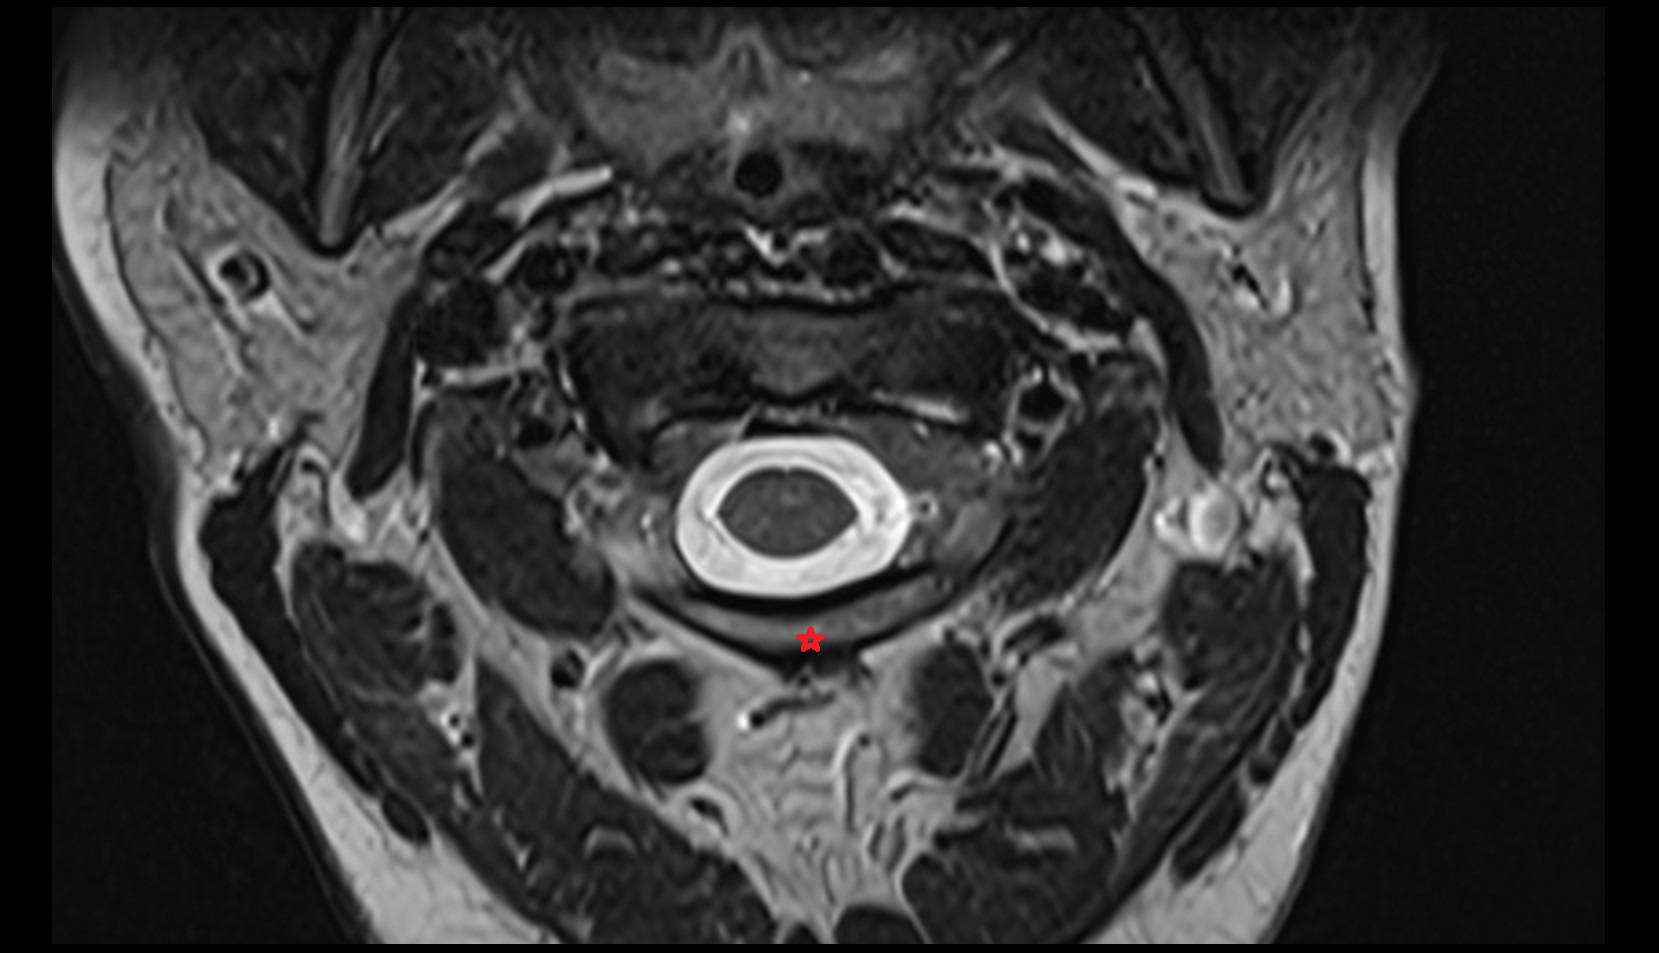

- Urinary bladder

- Uterus

- Cervix of uterus

- Vagina

- Rectum